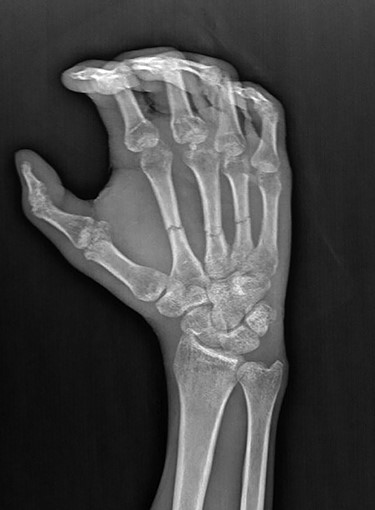

A 27-year-old male was admitted to the emergency room after blunt trauma on the dorsum of the right hand. In his physical examination, circulation and sensory findings were normal, but the motor functions were limited. On the X-ray radiograph, metacarpal base fractures were detected in the index, middle and ring fingers (Figs 1 and 2). After the surgical area was sterilized, the dissection was initiated under tourniquet and general anesthesia. Tendons were found to be intact due to blunt trauma, and the metacarpal base fractures in fingers were exposed (Fig. 3). These bones were stabilized with Kirschner wires (Fig. 4). After the debridement of dead tissues and opening the tourniquet, bleeding was controlled, and skin was stapled. The flap was planned for the 2 x 2 cm defect, which corresponds to the third metacarpal bone and exposed the tendon and bone (Fig. 5). The first dorsal metacarpal artery (FDMA) flap was initially considered; however, a dorsoradial artery flap was preferred since the dissection reached to the second metacarpal bone.